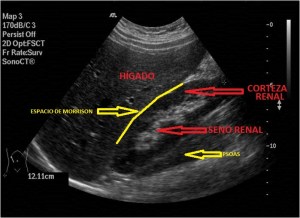

Sabes esto que estás en la playa y quieres hacer una foto, pones el teléfono y te das cuenta que te sale un trocito de nada de playa, pones el teléfono apaisado y entra un poco más, pero no te entra la puesta de Sol, la orilla y las olas…¿cómo lo solucionas?…lo solucionas con una imagen panorámica que es una función de tu cámara donde tú haces una foto y empiezas a mover el teléfono suavemente sin perder la línea del horizonte y cuando has capturado toda la escena paras, el resultado es este:

Con la eco pasa igual…cuando queremos estudiar, por ejemplo, el recto anterior del muslo en axial,perfecto…pero en longitudinal, como la imagen 2, se complica porque desde la rótula a la inserción en la cadera, tenemos mucho recorrido. En este caso hacemos lo mismo que cuando hacemos la foto del atardecer…nos ponemos en un extremo, activamos la funciona, recorremos suave y continuamente por la anatomía que queremos fotografiar y ya está…mira la pantalla y no el movimiento de tu mano,como si hicieses la foto, ves la pantalla,pero no como mueves el teléfono.

Técnicamente es lo mismo, ambos dispositivos hacen una suma de imágenes que se plasman en un resultado final estupendo. Toda la escena más pequeña, pero más alargada que te da percepción de toda la magnitud de aquello que pretendes estudiar, te quita algo de detalle, pero te sirve para medir perfectamente y además puedes incrementar y mover la imagen con tu track ball…